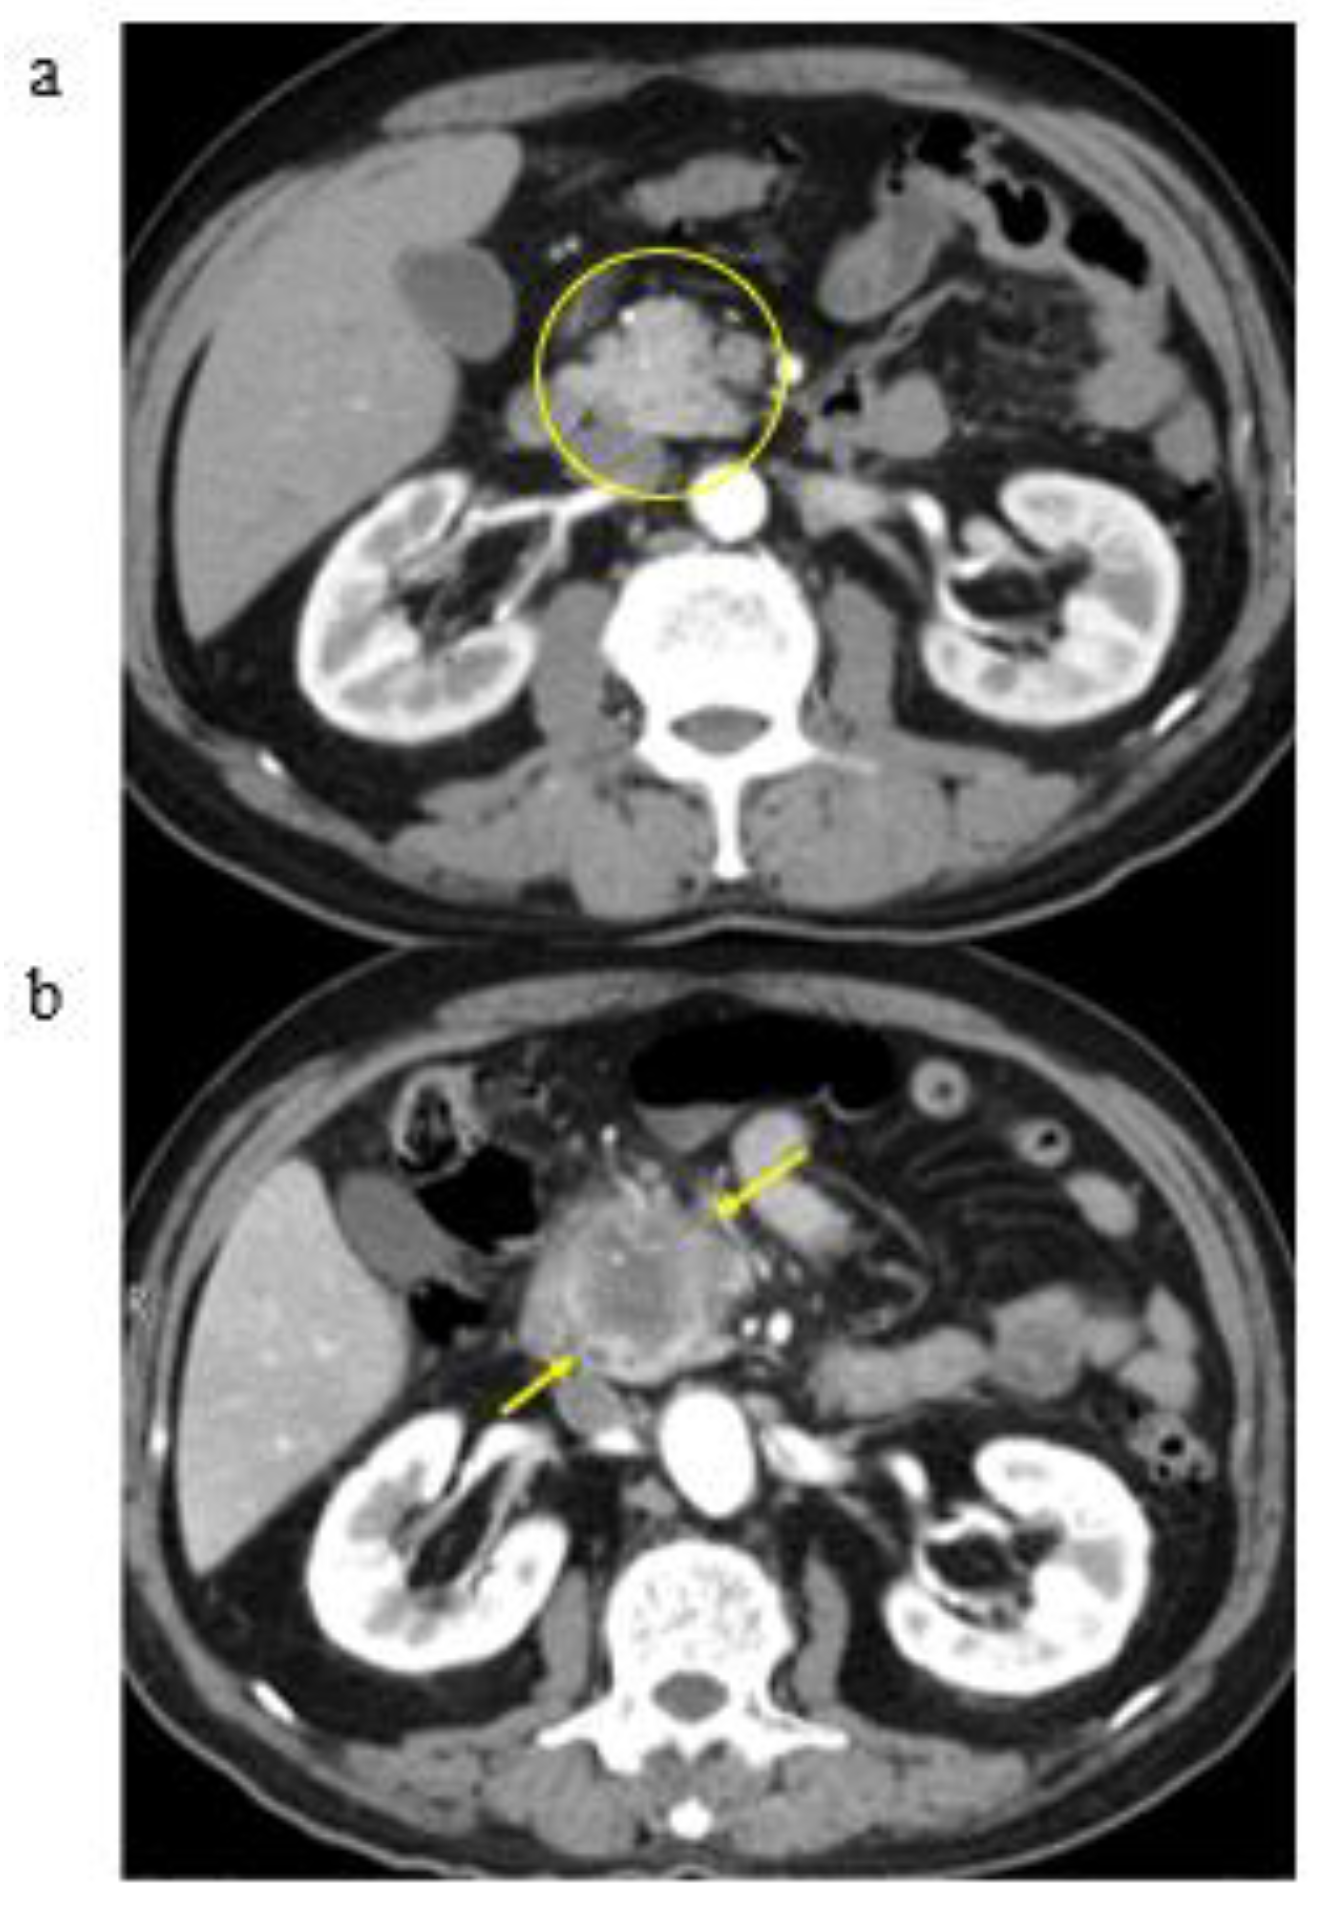

3.2. A Representative Case and Classification by Specific Abnormality of the Pancreas

3.3. Time to Development of Pancreatic Cancer